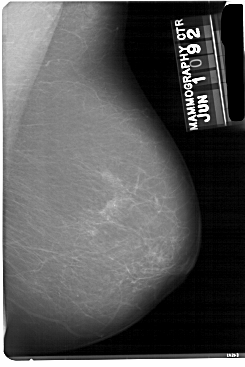

A_1864_1.RIGHT_MLO

RIGHT_CC LINES 5491 PIXELS_PER_LINE 3706 BITS_PER_PIXEL 12 RESOLUTION 43.5 NON_OVERLAY